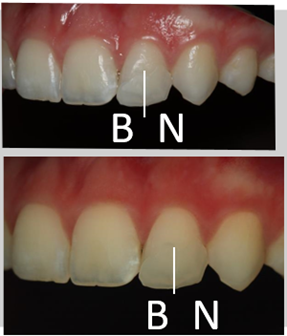

Prueba de color.

Fotografía normal y polarizada: los colores brillantes se mezclan mejor por su valor mayor.